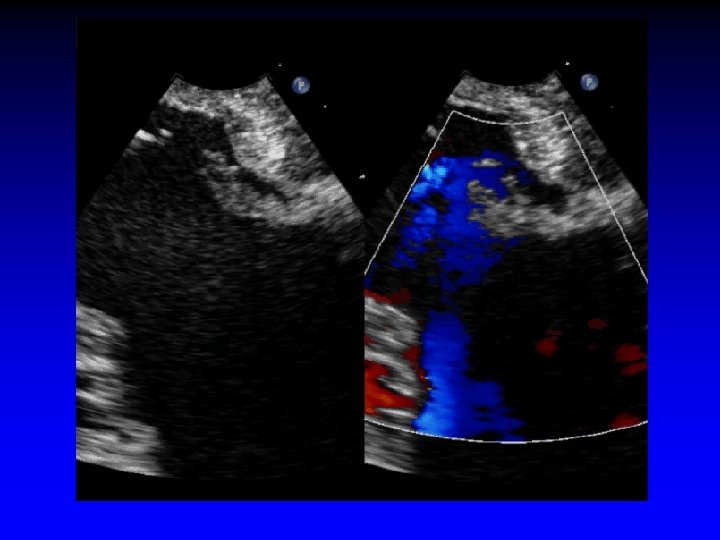

Case 3 Ruptured cords A 2 and A 3

Surgeon’s roadmap A 2 and A 3